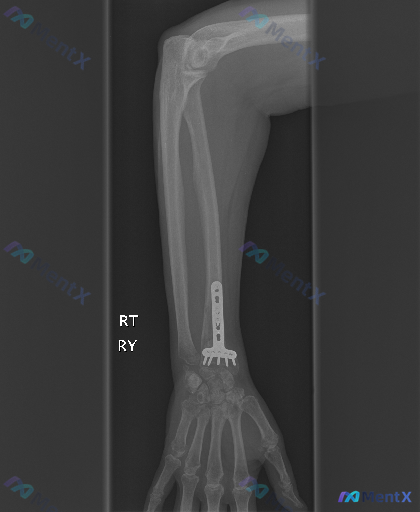

整理到一份左侧桡骨远端骨折术后的影像资料,大家一起讨论看看后续关注点应该放在哪里。 基本背景 左侧桡骨远端骨折,已行掌侧锁定加压钢板+螺钉内固定术。 本次影像(侧位X光)核心所见 1. 内固定:钢板位于桡骨远端掌侧,多枚螺钉在位,位置良好,未见明显松动、断裂或移位;螺钉末端在关节面下方,未明显进入关...

整理到一份右前臂及手部的影像学资料,背景是右桡骨远端骨折术后,目前只有正位片的描述。 关键影像发现: 1. 桡骨远端掌侧可见解剖型锁定接骨板及多枚螺钉,位置居中,未见明显钢板断裂或螺钉松动退出; 2. 桡骨远端骨折区域骨折线模糊,可见初步骨痂生长影,骨皮质连续性基本恢复;尺骨及桡骨干其余部分完整,腕...